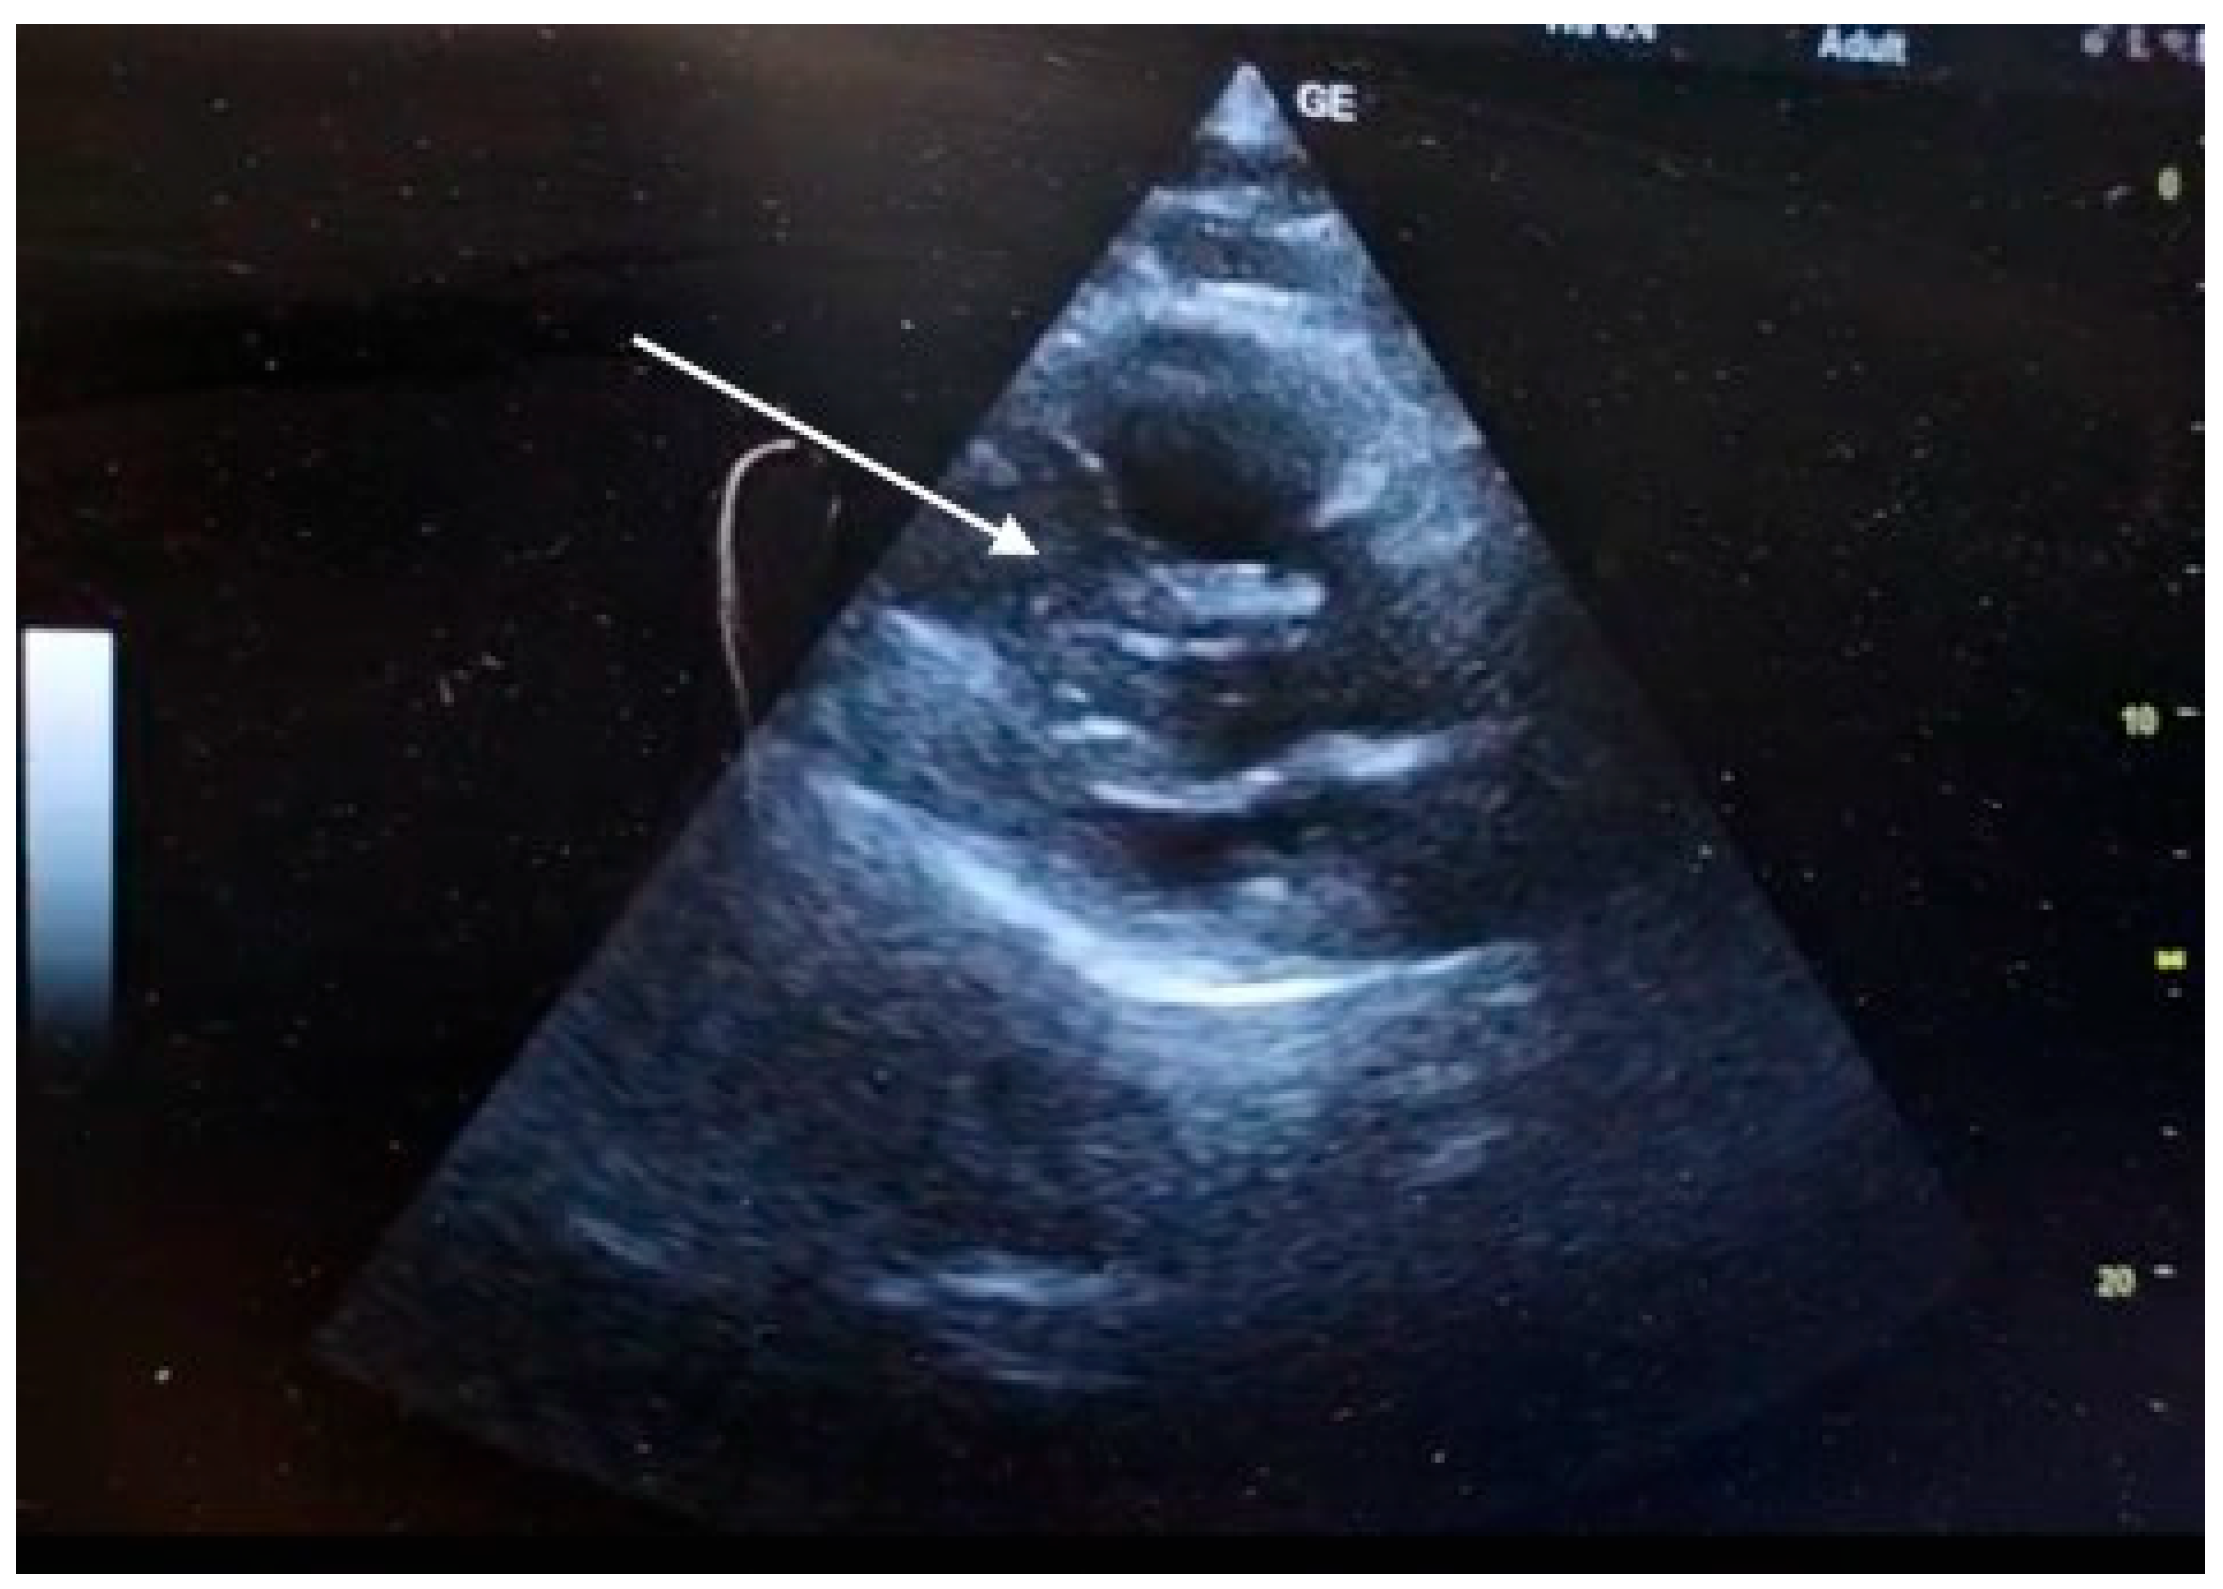

Safety surveillance during and immediately after the infusion confirmed the absence of major bleeding complications, with specific exclusion of intracranial hemorrhage. A follow-up transthoracic echocardiogram performed two hours after thrombolysis initiation confirmed the primary therapeutic endpoint - complete resolution of the mobile right atrial thrombus. Additionally, there was evidence of partial reversal of right ventricular pressure overload, demonstrated by a reduction of the RV/RA gradient from 40 mmHg to 28 mmHg (Figure 4).

Figure 4. POCUS - TTE post-thrombolysis. Complete resolution of intracardiac thrombus following Emergency Department thrombolysis. Follow-up TTE (apical four-chamber view) performed two hours after Alteplase infusion demonstrates complete clearance of the right atrium (RA), with no residual mobile thrombus visible.